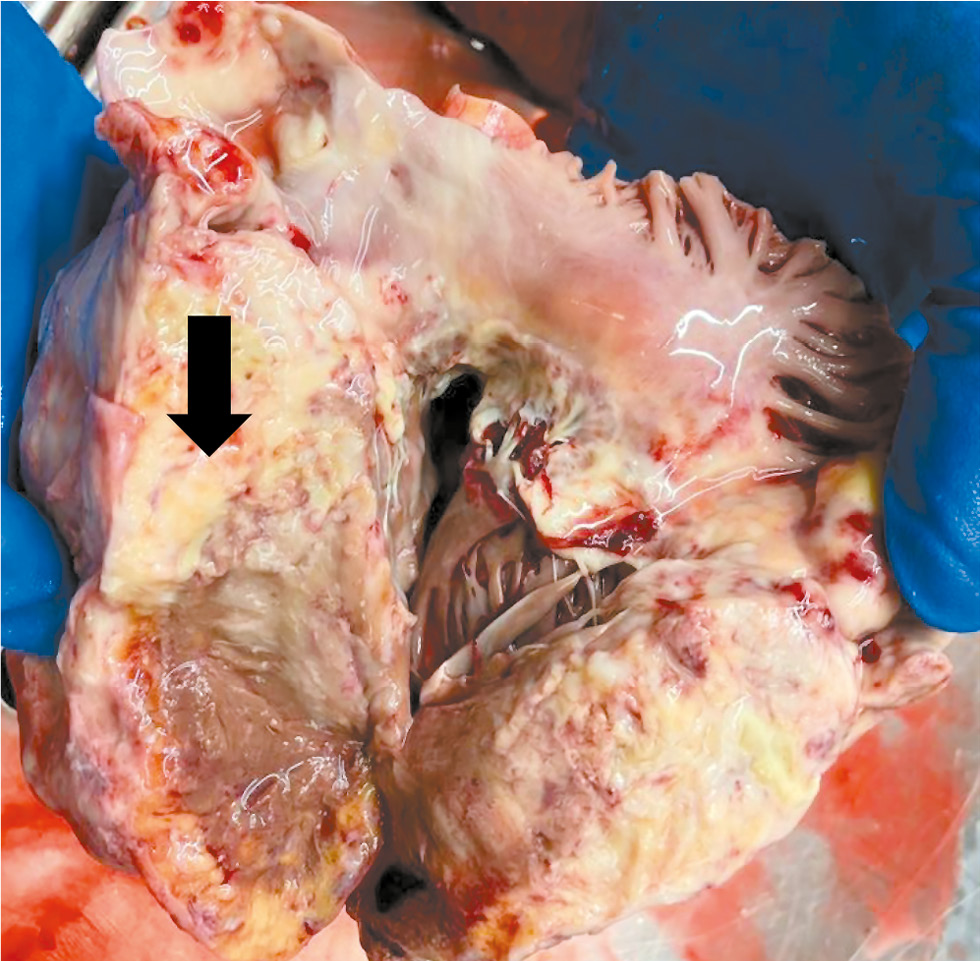

Однако по результатам аутопсии основным заболеванием установлена лимфома Ходжкина. Обнаружено значительное увеличение лимфоузлов средостения и опухолевый конгломерат размерами 14×7×6,5 см в области расположения бифуркационных и прикорневых лимфоузлов. Диффузный рост серовато-белесоватой плотноэластичной ткани наблюдался в жировой клетчатке средостения, в зоне бифуркации трахеи и корней лёгких с распространением на сосудистый пучок основания сердца и прилежащий перикард (рис. 6). На перикарде и эпикарде отмечен налёт фибрина, со стороны эпикарда обращали на себя внимание множественные узловые разрастания опухолевой ткани (рис. 7). Также опухолевая ткань в виде узлов с тромботическими наложениями выступала в полость ПП. Выявлены тромбы единичных мелких ветвей лёгочных артерий. В миокарде ПЖ и МЖП обнаружен рост опухолевой ткани, замещающей миокард, с прорастанием эндокарда, корня аорты, истока лёгочной артерии (рис. 8). В миокарде ЛЖ от эпикарда и интрамурально — также участки разрастания опухолевой ткани. В зонах опухолевого роста толщина стенки ЛЖ составила 1,8–1,9 см, правого — до 1,5 см. Гистологическое исследование тканей позволило выявить диффузную полиморфноклеточную инфильтрацию и клетки Ходжкина и Рида–Березовского–Штернберга (рис. 9), также опухолевые клетки определены в составе тромбов (рис. 10). В плевральных полостях обнаружено значительное количество жидкости (слева — 1100 мл, справа — 1500 мл). Следует отметить, что в коронарных артериях присутствовал распространённый (более 50% площади) атеросклеротический процесс, однако бляшки были стабильными, в стадии обызвествления, со стенозами до 50%.

Рис. 6. В области корней лёгких и сосудистого пучка основания сердца диффузный опухолевый рост.

Fig. 6. Diffuse tumor growth in the area of the roots of the lungs and the vascular bundle of the base of the heart.

Рис. 8. Миокард правого желудочка на разрезе с диффузным опухолевым ростом.

Fig. 8. The right ventricular myocardium is incised with diffuse tumor growth.